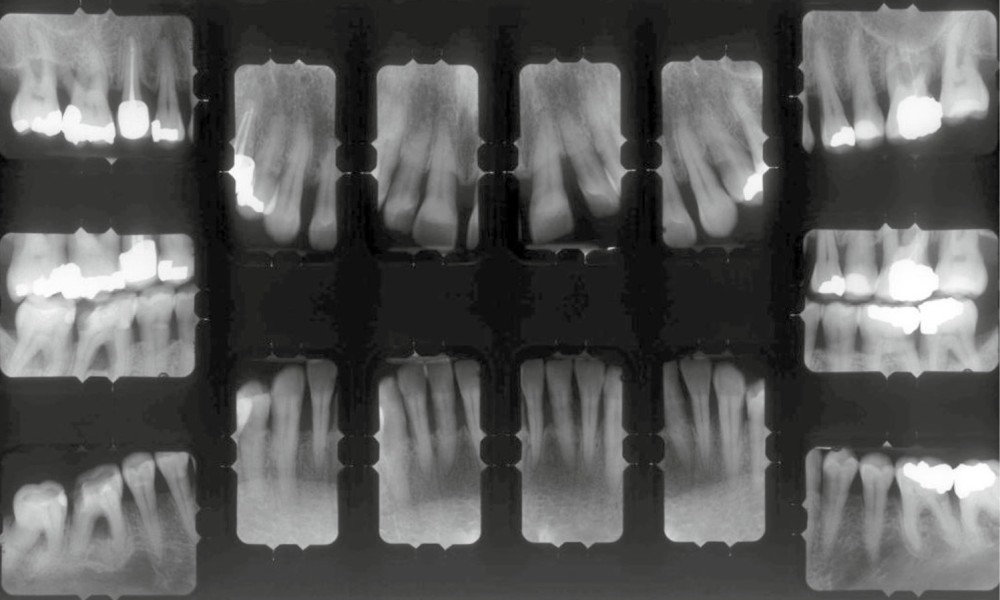

L’examen radiographique (fig. 3-5) nous indique une Classe I squelettique de Ballard (ANB 0°) sur un schéma facial à tendance hyperdivergent (FMA 28°). L’analyse céphalométrique confirme la vestibulo-version incisive (I/SN 111° ; IMPA 94°). La lyse osseuse est généralisée.